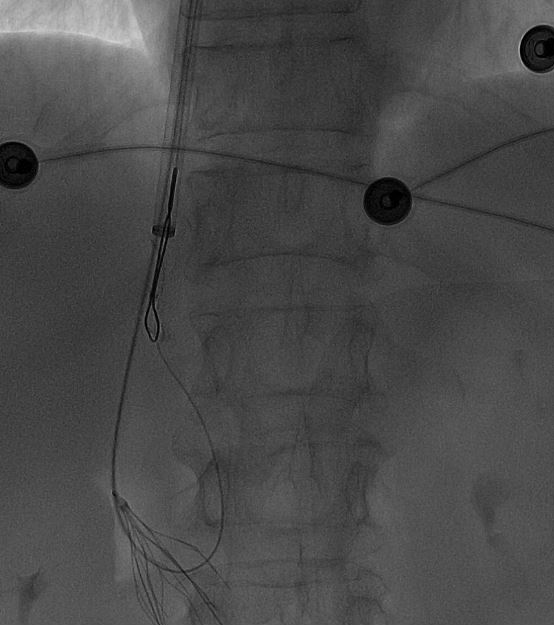

一切准备就绪后,田轩带领介入诊疗团队为阿婆实施下腔静脉滤器取出术。

术中,团队在影像设备的精准引导下,娴熟操作介入器械,精准定位倾斜的滤器,避开血管周边组织,逐步完成滤器的调整、抓取与取出操作。

整个手术过程十分顺利,未出现任何血管损伤等意外情况,这枚让阿婆和家属忧心许久的“困难”滤器被成功取出,术后阿婆生命体征平稳,身体状况良好。